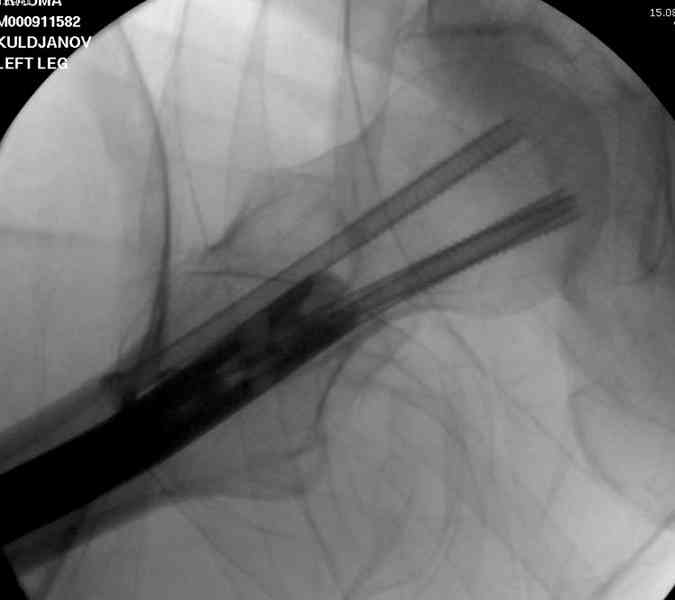

В первый же день произведено антеградное штифтованием DePuy Trochanteric Nail.

На второй день (7) обнаружен пропущенный перелом,

и проведены шурурпы через и спереди штифта без удаления.

Послеоперационные снимки